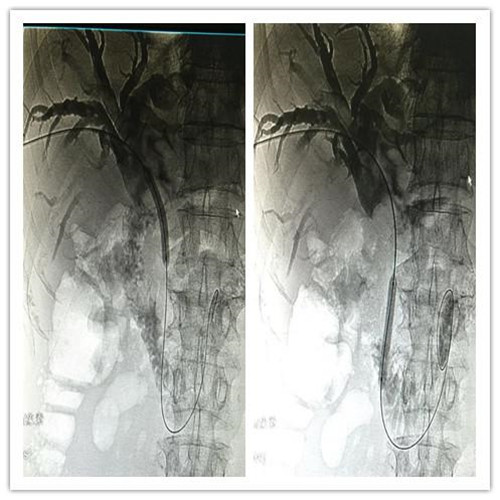

患者全身皮肤金黄瘙痒难忍,在B超定位下行肝内胆管引流术、术后因引流不畅拔管;在胃镜下逆行ERCP胆管支架植入术,经过术者反复操作,但导丝无法通过病变段。看到患者痛苦不堪,家属迫切治疗的场面,介入科李建国主任现场会诊提出为患者在介入下行PTCD治疗的意见。术前经过讨论制定多套严密方案,与患者及家属多方沟通达成介入手术共识;术中精准定位穿刺选择不同的导丝、导管多角度旋转闭塞原地不动,时间一分一分过去......在医护人员努力下,闭塞的胆道开通了,再经球囊分段扩张病变狭窄段,内外引流管放置顺利300余毫升的黑褐色胆汁流出......

在护理人员精心的配合下,手术历时30余分钟圆满成功,彻底解决了患者梗阻性黄疸引发的皮肤黄染,保护了肝功能。

顺行开通高位胆管梗阻性黄胆经皮肝穿胆管引流术优势明显